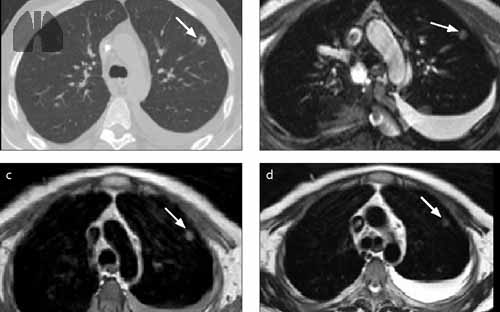

Methods 28 patients (10–27 years) with CF lung disease performed non-enhanced chest MRI, spirometry and multiple breath washout (MBW). Images acquired at end-inspiration and end-expiration were registered by optical flow to estimate expiratory-inspiratory proton density change (Δ1H-MRI) as a measure of regional ventilation. MR images were also evaluated using a CF-specific scoring system.

Results Biomarkers of CF ventilation impairment were defined from Δ1H-MRI: Δ1H-MRI median, Δ1H-MRI quartile coefficient of variation (QCV) and percent low-ventilation volume (%LVV). Imaging biomarkers correlate to all the clinical measures of ventilation abnormalities, with the strongest correlation between Δ1H-MRI median and forced expiratory volume in one second (FEV1) (r2=0.44, p<0.001), Δ1H-MRI QCV and lung clearance index (LCI) (r2=0.51, p<0.001) and %LVV and LCI (r2=0.66, p<0.001). Correlations were also found between imaging biomarkers of ventilation and morphological scoring.